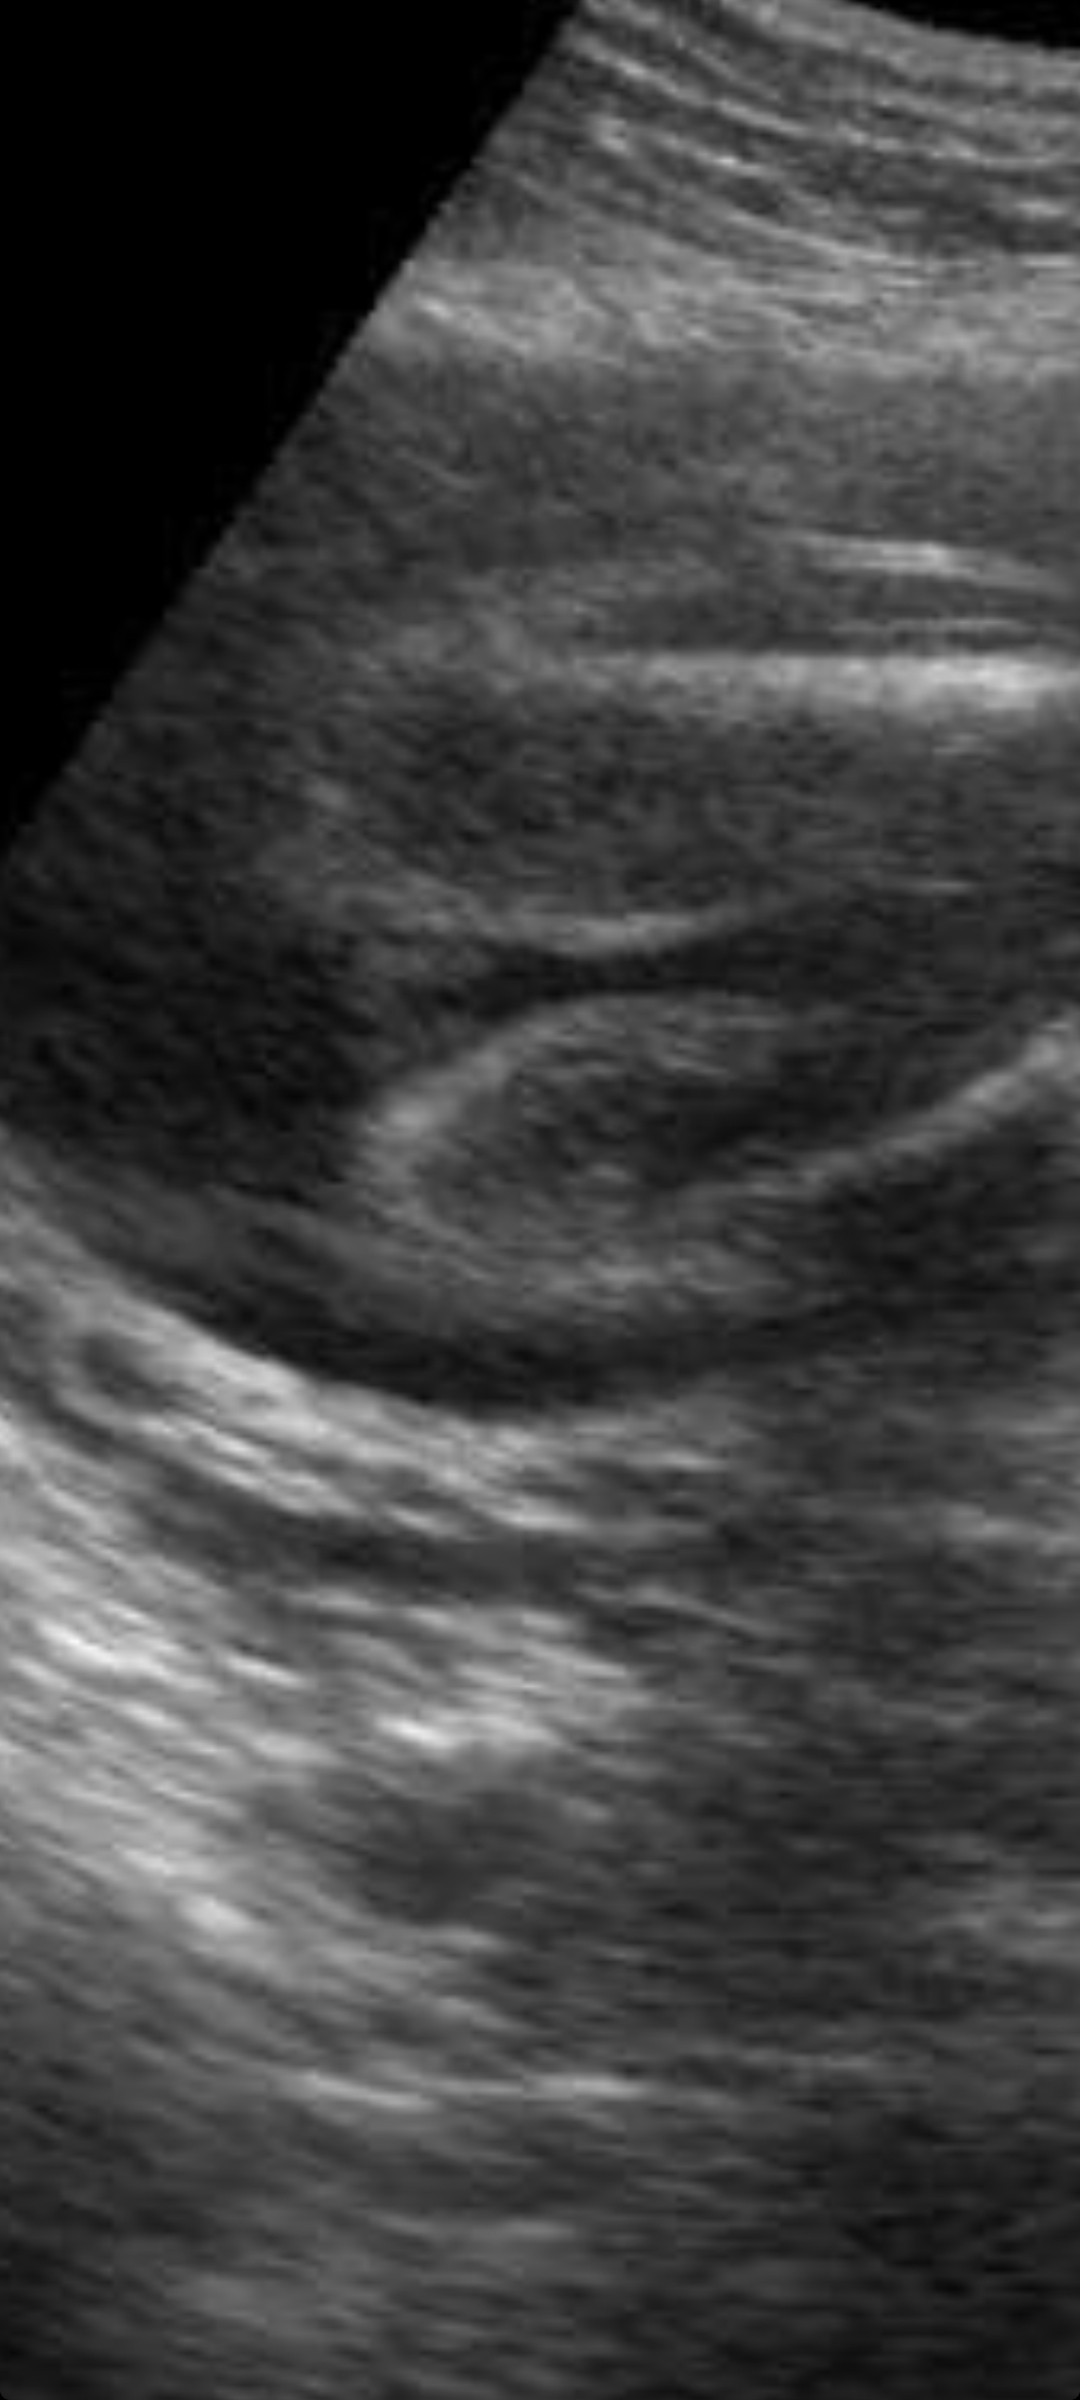

Cześć, mam pytanie. Dwóch lekarzy powiedziało mi, że będę mieć córeczkę, aczkolwiek mam wątpliwości. Po przybliżeniu zdjęcia coś tam zauważyłam :) Jak myślicie? Mogę mieć jakieś obawy, czy raczej sobie wymyślam?

Podobno jak są tam dwie kreseczki to dziewczynka, moim zdaniem są dwie kreseczki.

Ja mam synka i usg wygladało zdecydowanie inaczej.